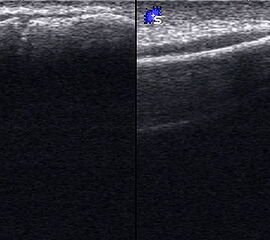

Abgehobenes Periost mit periostalem Hämatom (rechts) mit Gegenseite (links). Die Kortikalis wird unterbrochen von der noch offenen Wachstumsfuge der Fibula.

Abbildung 12

Lagerung: Rückenlage, leichte Innrotation des Fußes.

Schnittebene: LS über distaler Fibula.

Referenzstruktur: Fibula im Längsverlauf.

Befunde: Bei Kindern wird nach Distorsion des OSG mitunter eine Lösung der Fibulafuge vermutet, die jedoch in der klinischen Praxis sehr selten ist. Die seitenvergleichende Untersuchung zeigt dann ein aufgrund des dicken und bei Kindern gut abgrenzbaren echogenen Periosts ein periostales Hämatom, was aber auch ein Hinweis auf eine Fissur oder Fraktur sein kann (Abb.12).